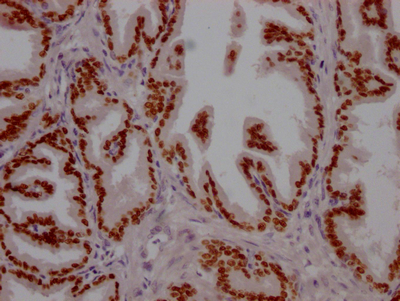

ApplicationELISA, WB, IHC, IP; Recommended dilution: WB:1:500-1:5000, IHC:1:50-1:200, IP:1:200-1:1000